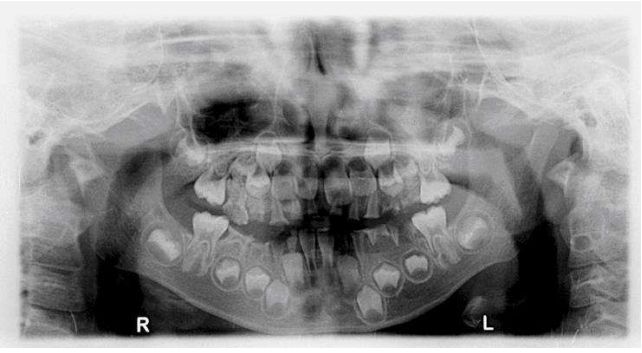

66.15歲女孩丙下顎前方有一個無疼痛的腫脹而來求診,經X光檢査如附圖所示,病變區切片後,病理診斷為齒 源性角化囊腫,則此病患最可能罹患下列何種疾病? (A)艾迪森氏病(Addison's disease) (B)天使症(cherubism) (C)麥克滾-阿爾布萊德氏症候群(McCune-Albright syndrome) (D)痣樣基底細胞癌症候群(nevoid basal cell carcinoma syndrome)